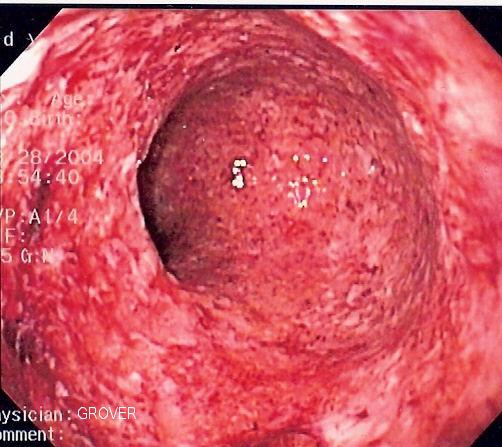

Crohn's Disease vs Colitis ulcerosaWer an einer chronisch entzündlichen Darmerkrankung (CED) leidet, sollte jährlich zur Darmspiegelung (Koloskopie).

Diese Patienten haben ein erhöhtes Risiko für kolorektale Karzinome (Dick-/Enddarmkrebs)

Durch die chronische Entzündung und oftmals auch durch die begleitende immunsuppressive Therapie, welche das körpereigene Immunsystem unterdrückt, so dass sich die Autoimmunerkrankungen im Rahmen hält, wird die Tumorüberwachungsleistung des Immunsystems deutlich geschädigt.